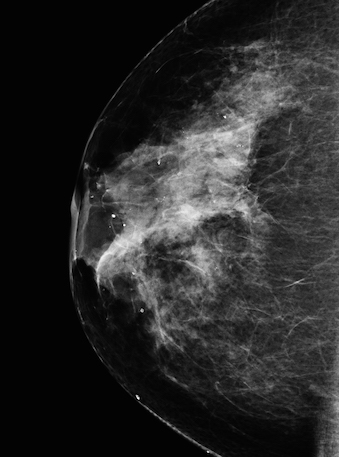

While identifying cat photos seems like a trivial goal, the same approach can be used across many important domains. Instead of identifying cat photos, machine learning could be used to identify breast cancer in the imagery generated during a mammogram. Beyond image recognition, machine learning has also been used for natural language processing, speech recognition, and predictive analytics, among other tasks.

This is a Mammogram